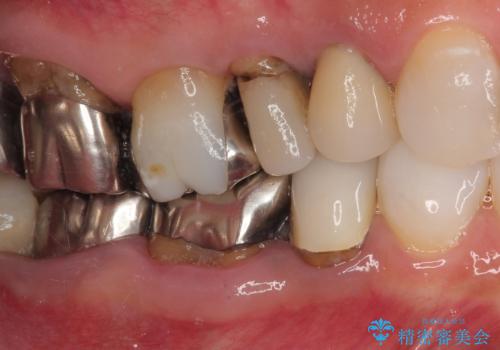

- むし歯の放置期間が長く、クラウンの幅が狭くなってしまった歯を気にして来院された患者様です。

細長いクラウンの周りが汚れてきたこと、奥の銀歯が笑ったときに見えることから、3本をセラミッククラウンにて補綴し、大きさのバランスを整えることとしました。